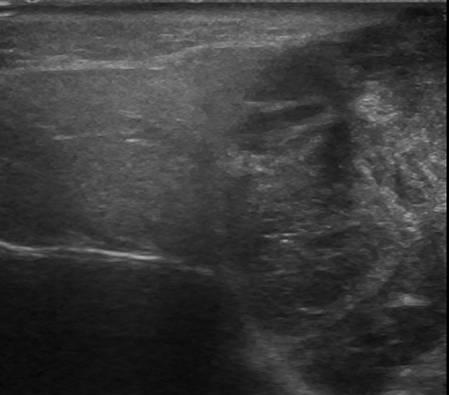

U tuyến nước bọt

» Thông tin: Nam giới – 79 tuổi.

» Lâm sàng: Khối vùng mang tai / K thực quản.

# Di căn tuyến nước bọt mang tai.